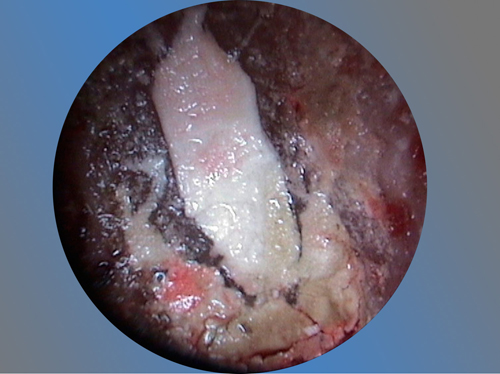

Es una intervención técnicamente exigente, que requiere formación e instrumentos especializados (microscopio, endoscopio, etc.), pero que correctamente realizada no causa molestias prácticamente y tiene unos resultados exitosos en más del 90% de los casos.

Los implantes son una buena herramienta, pero sin duda lo mejor son los propios dientes naturales. Con la cirugía periapical nuestros pacientes tienen la oportunidad de conservar sus propios dientes afectados de infección en el hueso periapical.